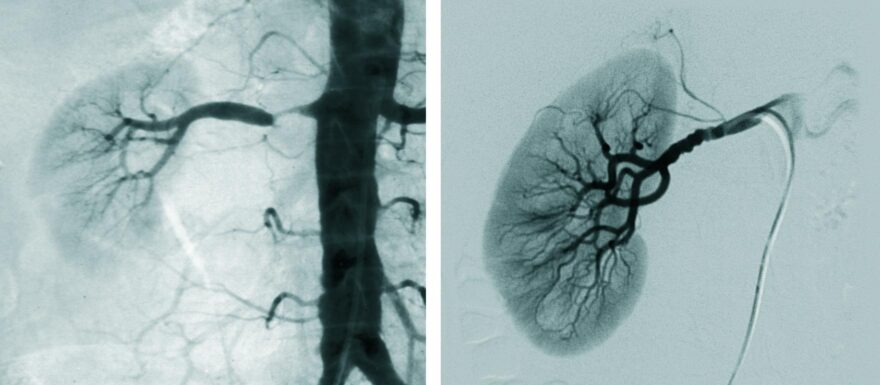

Een vernauwing van een of beide nierarteriën kan het gevolg zijn van fibromusculaire dysplasie, maar ontstaat meestal als uiting van gegeneraliseerde atherosclerose. Zolang de mate van stenosering beperkt blijft, zal de nier via aanpassing van de intrarenale hemodynamiek nog voor voldoende perfusie kunnen zorgen. Naarmate de stenose in ernst toeneemt, wordt het renine-angiotensinesysteem echter steeds meer geactiveerd en ontstaat er ischemische schade in de nier met uiteindelijk nierfunctieverlies. Een van de gevolgen van nierarteriestenose is hypertensie, waarschijnlijk door het verhoogde renine. Toch blijft nog een aanzienlijk percentage van de patiënten normotensief. Revascularisatie heeft bij patiënten met fibromusculaire dysplasie vaak wel een gunstig effect, maar het nut van deze therapie bij atherosclerotische afwijkingen wordt betwijfeld.